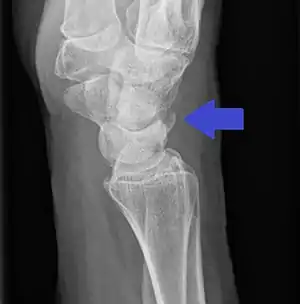

Triquetral avulsion fracture

Triquetral fractures can occur due to forceful flexion of the wrist, causing an avulsion of the dorsal aspect of the bone that is often hidden on anterior radiographs, but can be seen as a tiny bone fragment on lateral views.

Treatment is generally by casting for 4 to 6 weeks.[3]